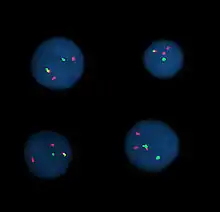

Fluorescence in situ hybridization

Fluorescence in situ hybridization (FISH) refers to using fluorescently labeled probe to hybridize to cytogenetic cell preparations.

This section refers to the preparation of standard cytogenetic preparations

The slide is aged using a salt solution usually consisting of 2X SSC (salt, sodium citrate). The slides are then dehydrated in ethanol, and the probe mixture is added. The sample DNA and the probe DNA are then co-denatured using a heated plate and allowed to re-anneal for at least 4 hours. The slides are then washed to remove the excess unbound probe, and counterstained with 4',6-Diamidino-2-phenylindole (DAPI) or propidium iodide.

Analysis

Analysis of FISH specimens is done by fluorescence microscopy by a clinical laboratory specialist in cytogenetics. For oncology, generally, a large number of interphase cells are scored in order to rule out low-level residual disease, generally between 200 and 1,000 cells are counted and scored. For congenital problems usually 20 metaphase cells are scored.